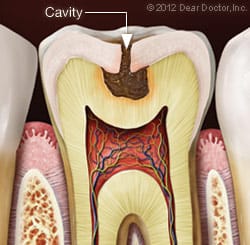

When a tooth experiences decay, it is often on the inside. Eventually the decay on the inside of a tooth reaches the outside, providing proof of a problem to the patient and dental professional in the form of a cavity. Fillings are made of materials that fill this void in order to stop the progression of decay and make the tooth strong again.